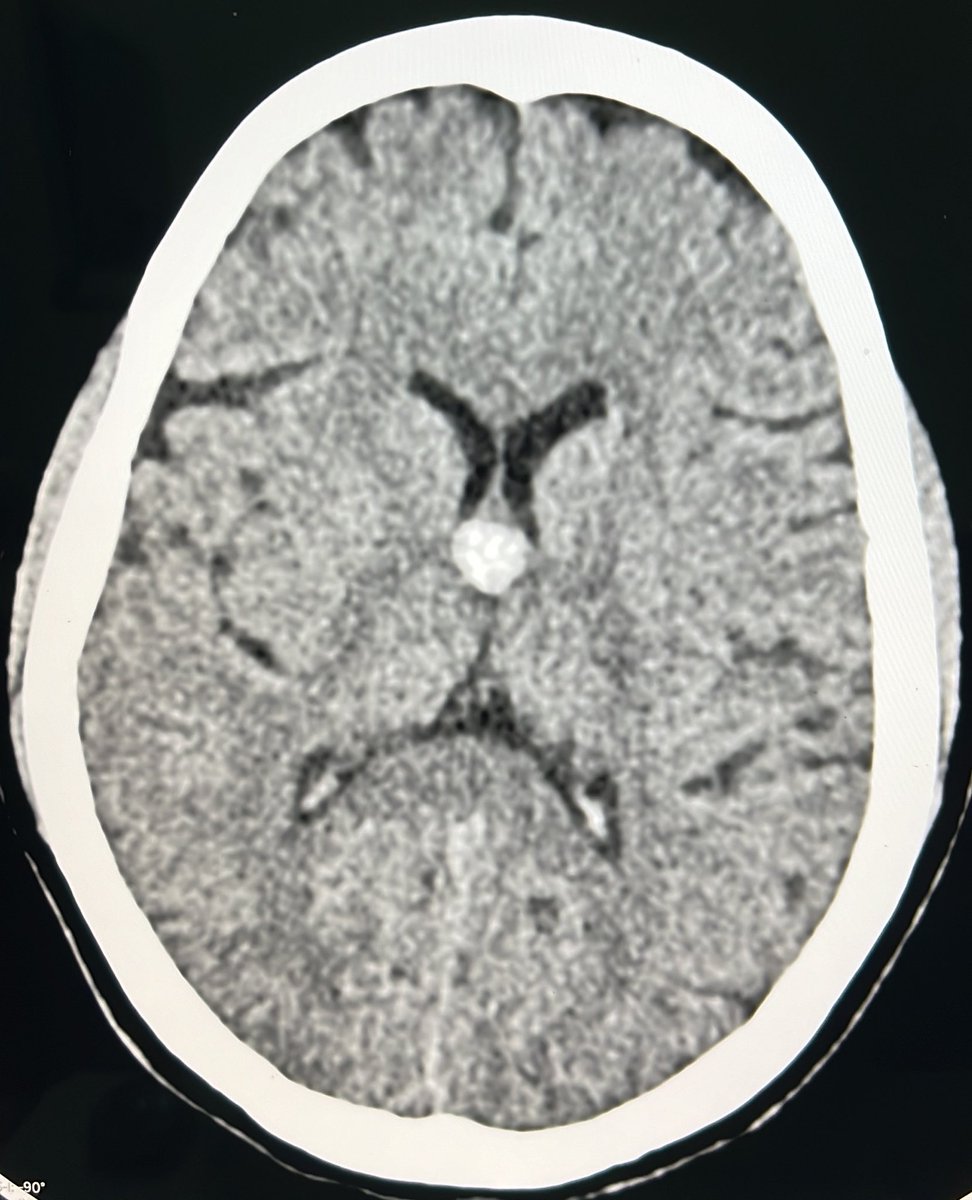

@RGovindiah

Govindiah R DMRD(DNB)

1 year

TB granuloma